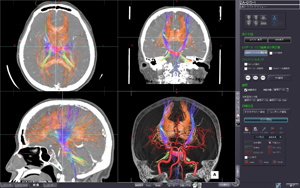

今回ITEMで初めて紹介されるziostation2の最新バージョンでは,従来から定評のある脳血流解析に加え,膵血流など体幹部の解析も可能にした「CT/MR血流解析」,「CTボリューム血流解析」,Dual Energy CT装置のデータを用いて抽出したい物質のCT値の範囲を指定しボリューム情報を分離する「D.E.デコンポジション」,神経線維の走行解析を行い,さらにMRAやCTAともフュージョン可能な「MRトラクトグラフィー」などを新たに搭載しました。より幅広い分野の検査をサポートします。 このほか,次期バージョンで搭載予定のMR心臓検査画像から右心室の機能解析を行う「MR右心機能解析」や 心壁の局所的な壁運動の異常を解析する「MRストレイン解析」なども紹介します。